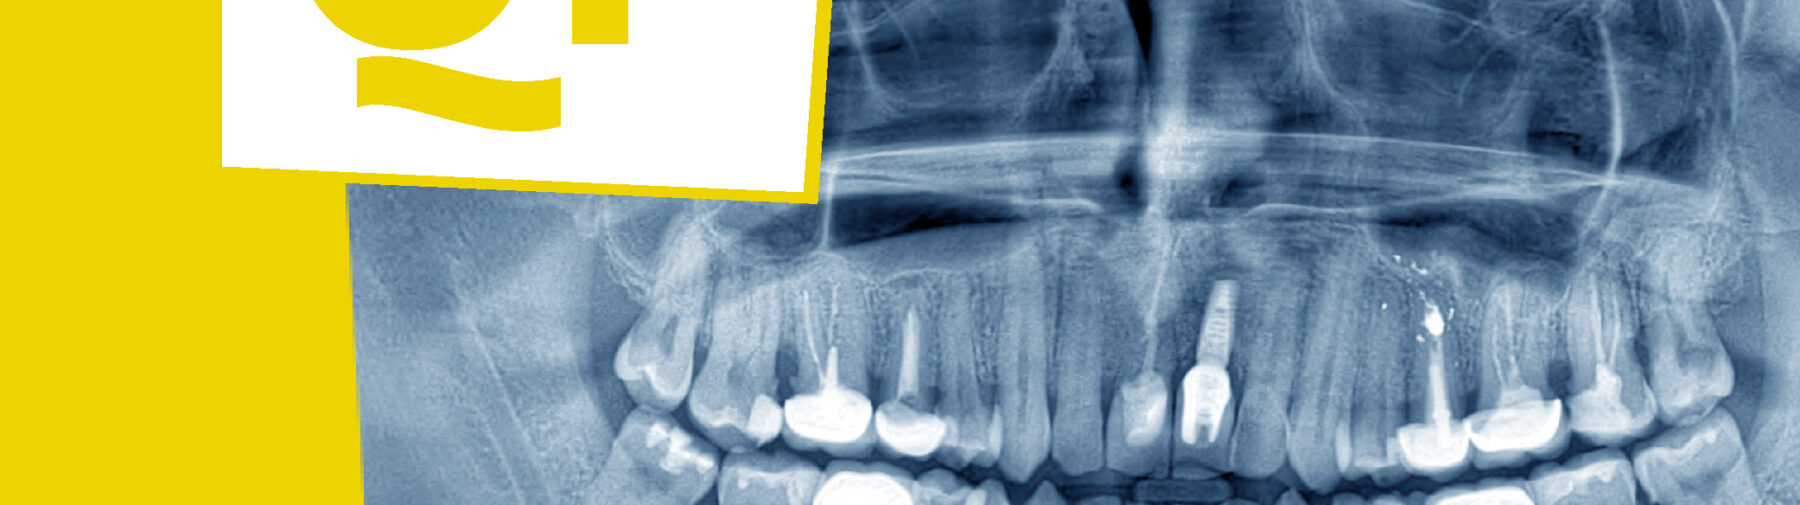

Tijdschrift | Nieuwste editie: Orale radiologie en digitale tandheelkunde

De nieuwste editie van het Quality Practice tijdschrift met als thema orale radiologie en digitale tandheelkunde is uit!

De snelle opkomst van de digitale tandheelkunde heeft de afgelopen jaren een stille, maar ingrijpende revolutie in de organisatie van de mondzorg ontketend. Vooral binnen de orale radiologie openen digitale beeldvorming en innovatieve diagnostische tools de deur naar meer precisie, uniformiteit en beter toegankelijke informatie. Dit sluit aan bij de missie om betere mondzorg mogelijk te maken door grensverleggende diagnostiek en digitale technologie; voor echte, gepersonaliseerde zorg. Maar waar staan we nu precies? Wat kan er al? En welke stappen moeten we nog zetten?

In deze uitgave maakt u kennis met de staat van de digitale tandheelkunde anno 2025. We onderzoeken de rol van kunstmatige intelligentie in diagnostiek en behandelplanning, verkennen digital twins en VR-simulatie voor onderwijs en evalueren digitale workflows met CAD/CAM-systemen en 3D-printing. Uiteraard stellen we de vraag: dragen deze innovaties bij aan betere behandeluitkomsten en duurzamere processen?

Eén van de artikelen zoomt in op specifieke AI-toepassingen binnen de orale radiologie, zoals cariësdetectie en het segmenteren van de canalis mandibularis. De winst in snelheid, consistentie en betrouwbaarheid lijkt indrukwekkend. Tegelijkertijd blijft één ding duidelijk: kritisch denken, ethiek en menselijk toezicht blijven onmisbaar. AI ondersteunt, maar de tandarts of mondhygiënist blijft de regisseur van de zorg.

Daarnaast leest u over een veelbelovende nieuwe vorm van diagnostiek: dental-decidated Magnetic Resonance Imaging (ddMRI). Een techniek die mogelijk een belangrijke rol gaat spelen bij het vroegtijdig opsporen van periapicale ontstekingen.

Bovendien neemt een bijzonder stuk casuïstiek u mee in de wereld van de CBCT-diagnostiek. Casusgestuurde analyses laten zien hoe driedimensionale beeldvorming kan leiden tot veiligere, verantwoorde diagnostiek en betere behandelingen.